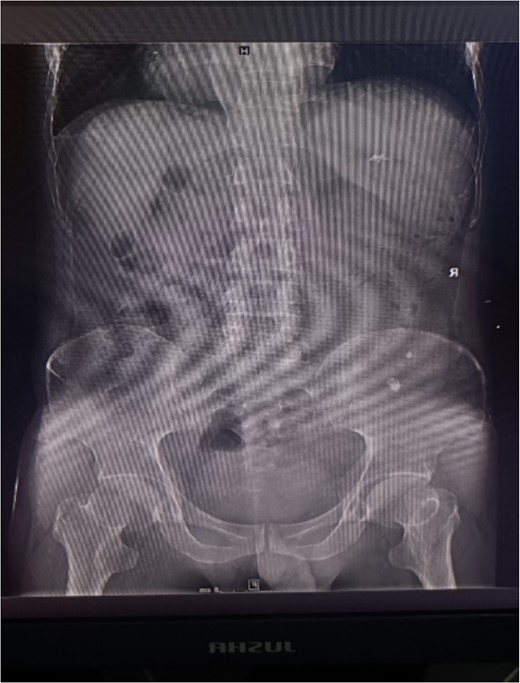

X-ray plain film showing multiple punctate stones in the right kidney area.

A 39-year-old man with kidney stones after kidney transplantation was admitted to our hospital on 29 November 2023. Eight years ago, he underwent a kidney transplant from a donor. Neither the donor nor the recipient had a history of kidney stones. The transplanted kidney was positioned in the right iliac fossa, and the patient had a successful postoperative recovery. However, a recent routine abdominal computed tomography (CT) scan revealed multiple stones in the transplanted kidney and bilateral in situ kidney atrophy. The stone was located in the lower calyx of the transplanted kidneys. Hydronephrosis was also observed. Kidney, ureter, and bladder radiographs showed multiple high-density speckles in the right kidney, the largest of which was ~0.5 cm in diameter. Physical examination (blood pressure, 147/91 mmHg; serum creatinine, 72.7 μmol/L; urea nitrogen, 5.1 mmol/L) revealed normal liver function, coagulation, and electrolytes. We suspected that these kidney stones were sizable and necessitated surgical intervention. Upon admission, pertinent examinations were conducted, and preoperative preparations were completed.